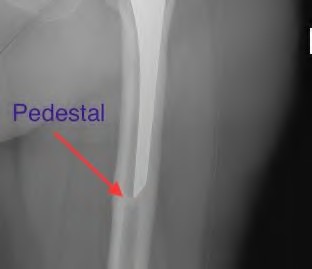

A 72-year-old female presents with progressive left thigh and knee pain for the last year. 5 years ago she sustained a femoral neck fracture treated with the implant seen in Figures A-C (current radiographs). The thigh pain is worse with weight-bearing. C-reactive

protein and erythrocyte sedimentation levels are within defined limits. Which of the following is the most likely cause of her pain?